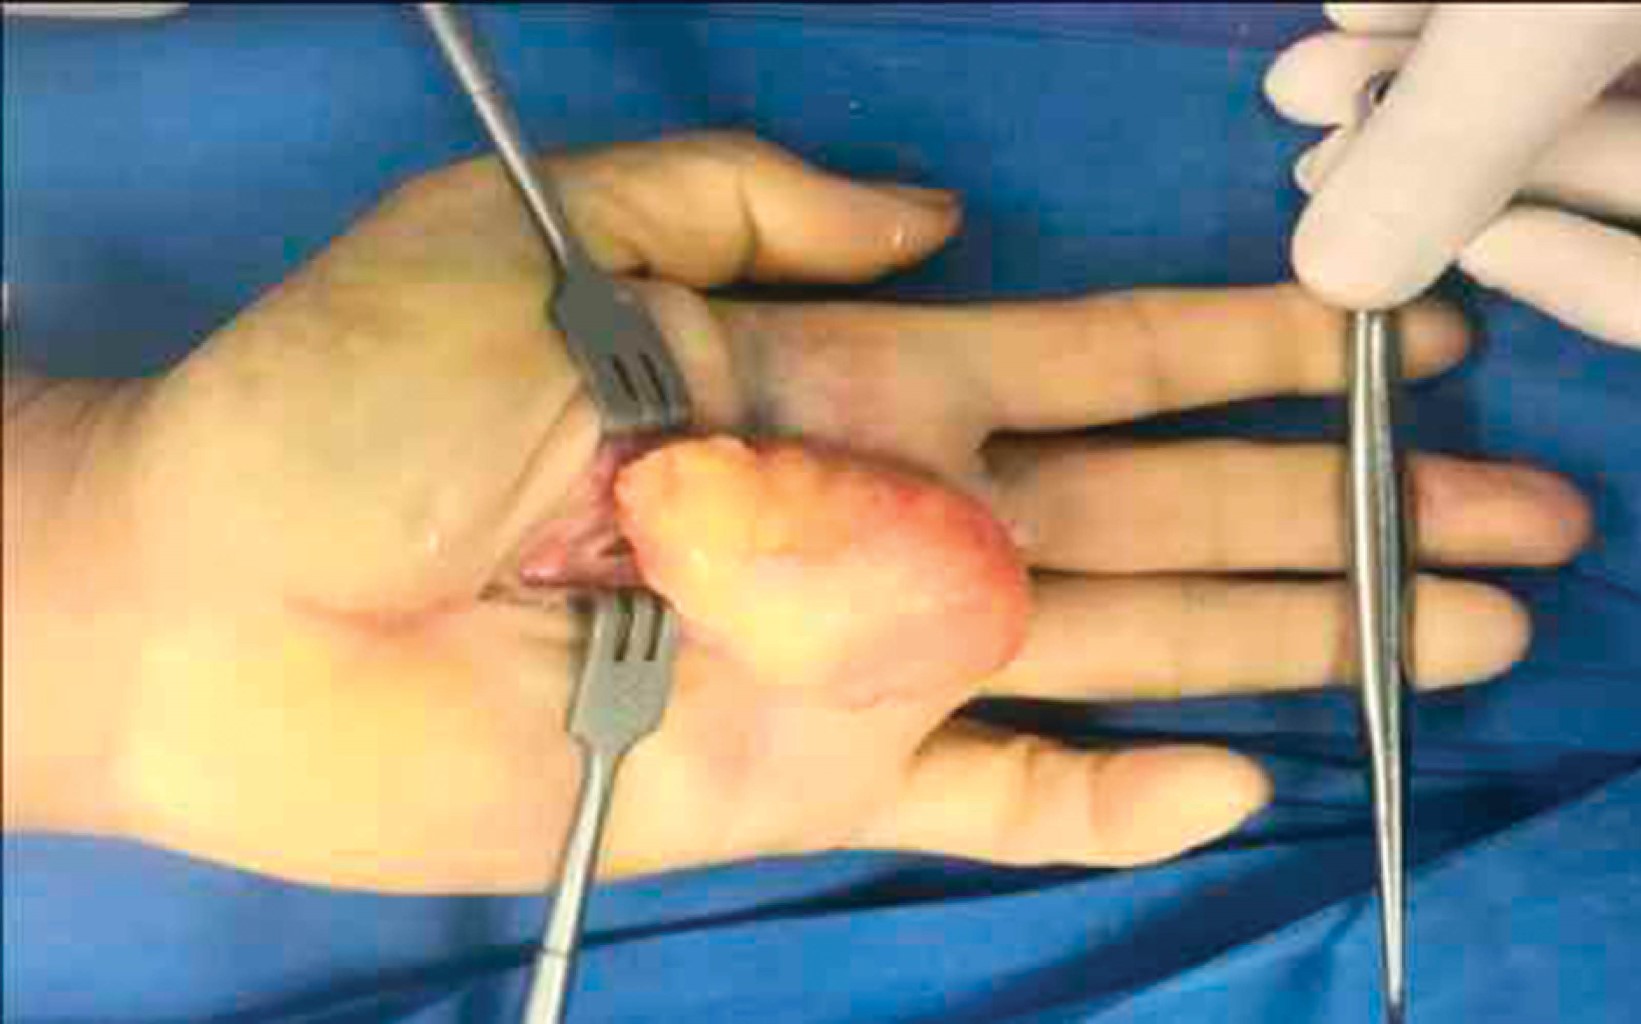

Se realizó electromiografía de la muñeca, la cual identificó aspectos compatibles con lesión marcada del nervio mediano izquierdo. Se decidió efectuar manejo quirúrgico por compresión extrínseca del nervio mediano. Se realizó resección quirúrgica de la tumoración de la eminencia tenar bajo sedación y bloqueo regional con isquemia, encontrando lesión superficial, solitaria, de bordes bien delimitados, redonda, movible, de consistencia blanda, color amarillo, con aspecto homogéneo semejante a tejido adiposo (Figura 3), con una delgada cápsula y medidas de 5 × 5.2 cm (Figura 4). Al realizar la exéresis de la lesión se observó integridad del flexor digitorum y ramas terminales del nervio mediano (Figura 5). Se envió a estudio histopatológico, mismo que reportó lipoma de patrón clásico (Figura 6).

Figura 3

Figura 4